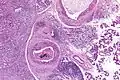

Low magnification micrograph of a salivary duct carcinoma with characteristic comedonecrosis (left of image) adjacent to normal parotid gland (right of image). H&E stain.